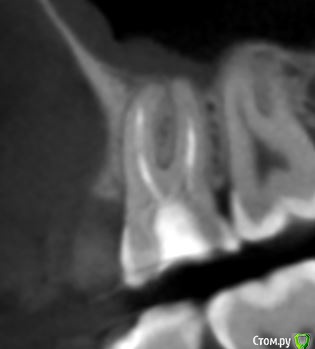

krokomot Опубликовано 19 февраля, 2020 Поделиться Опубликовано 19 февраля, 2020 в медиальном корне недопломбировка и наличие вероятно 4ого канала. Ссылка на комментарий

dmitrib81 Опубликовано 20 февраля, 2020 Автор Поделиться Опубликовано 20 февраля, 2020 Зуб делали много лет назад. Примерно неделю назад появились периодические боли, бывает целый день не болит, потом снова ноющая боль. С приёмом пищи никак не связано. На горячие и холод реакции нетПодскажите, может ещё прислать фоток из КТ Пикассо, а то я в этом ничего не понимаю, просто разных фото экрана прислал, без какого-либо понимания, на что смотреть.. Ссылка на комментарий

dmitrib81 Опубликовано 20 февраля, 2020 Автор Поделиться Опубликовано 20 февраля, 2020 еще фото Ссылка на комментарий